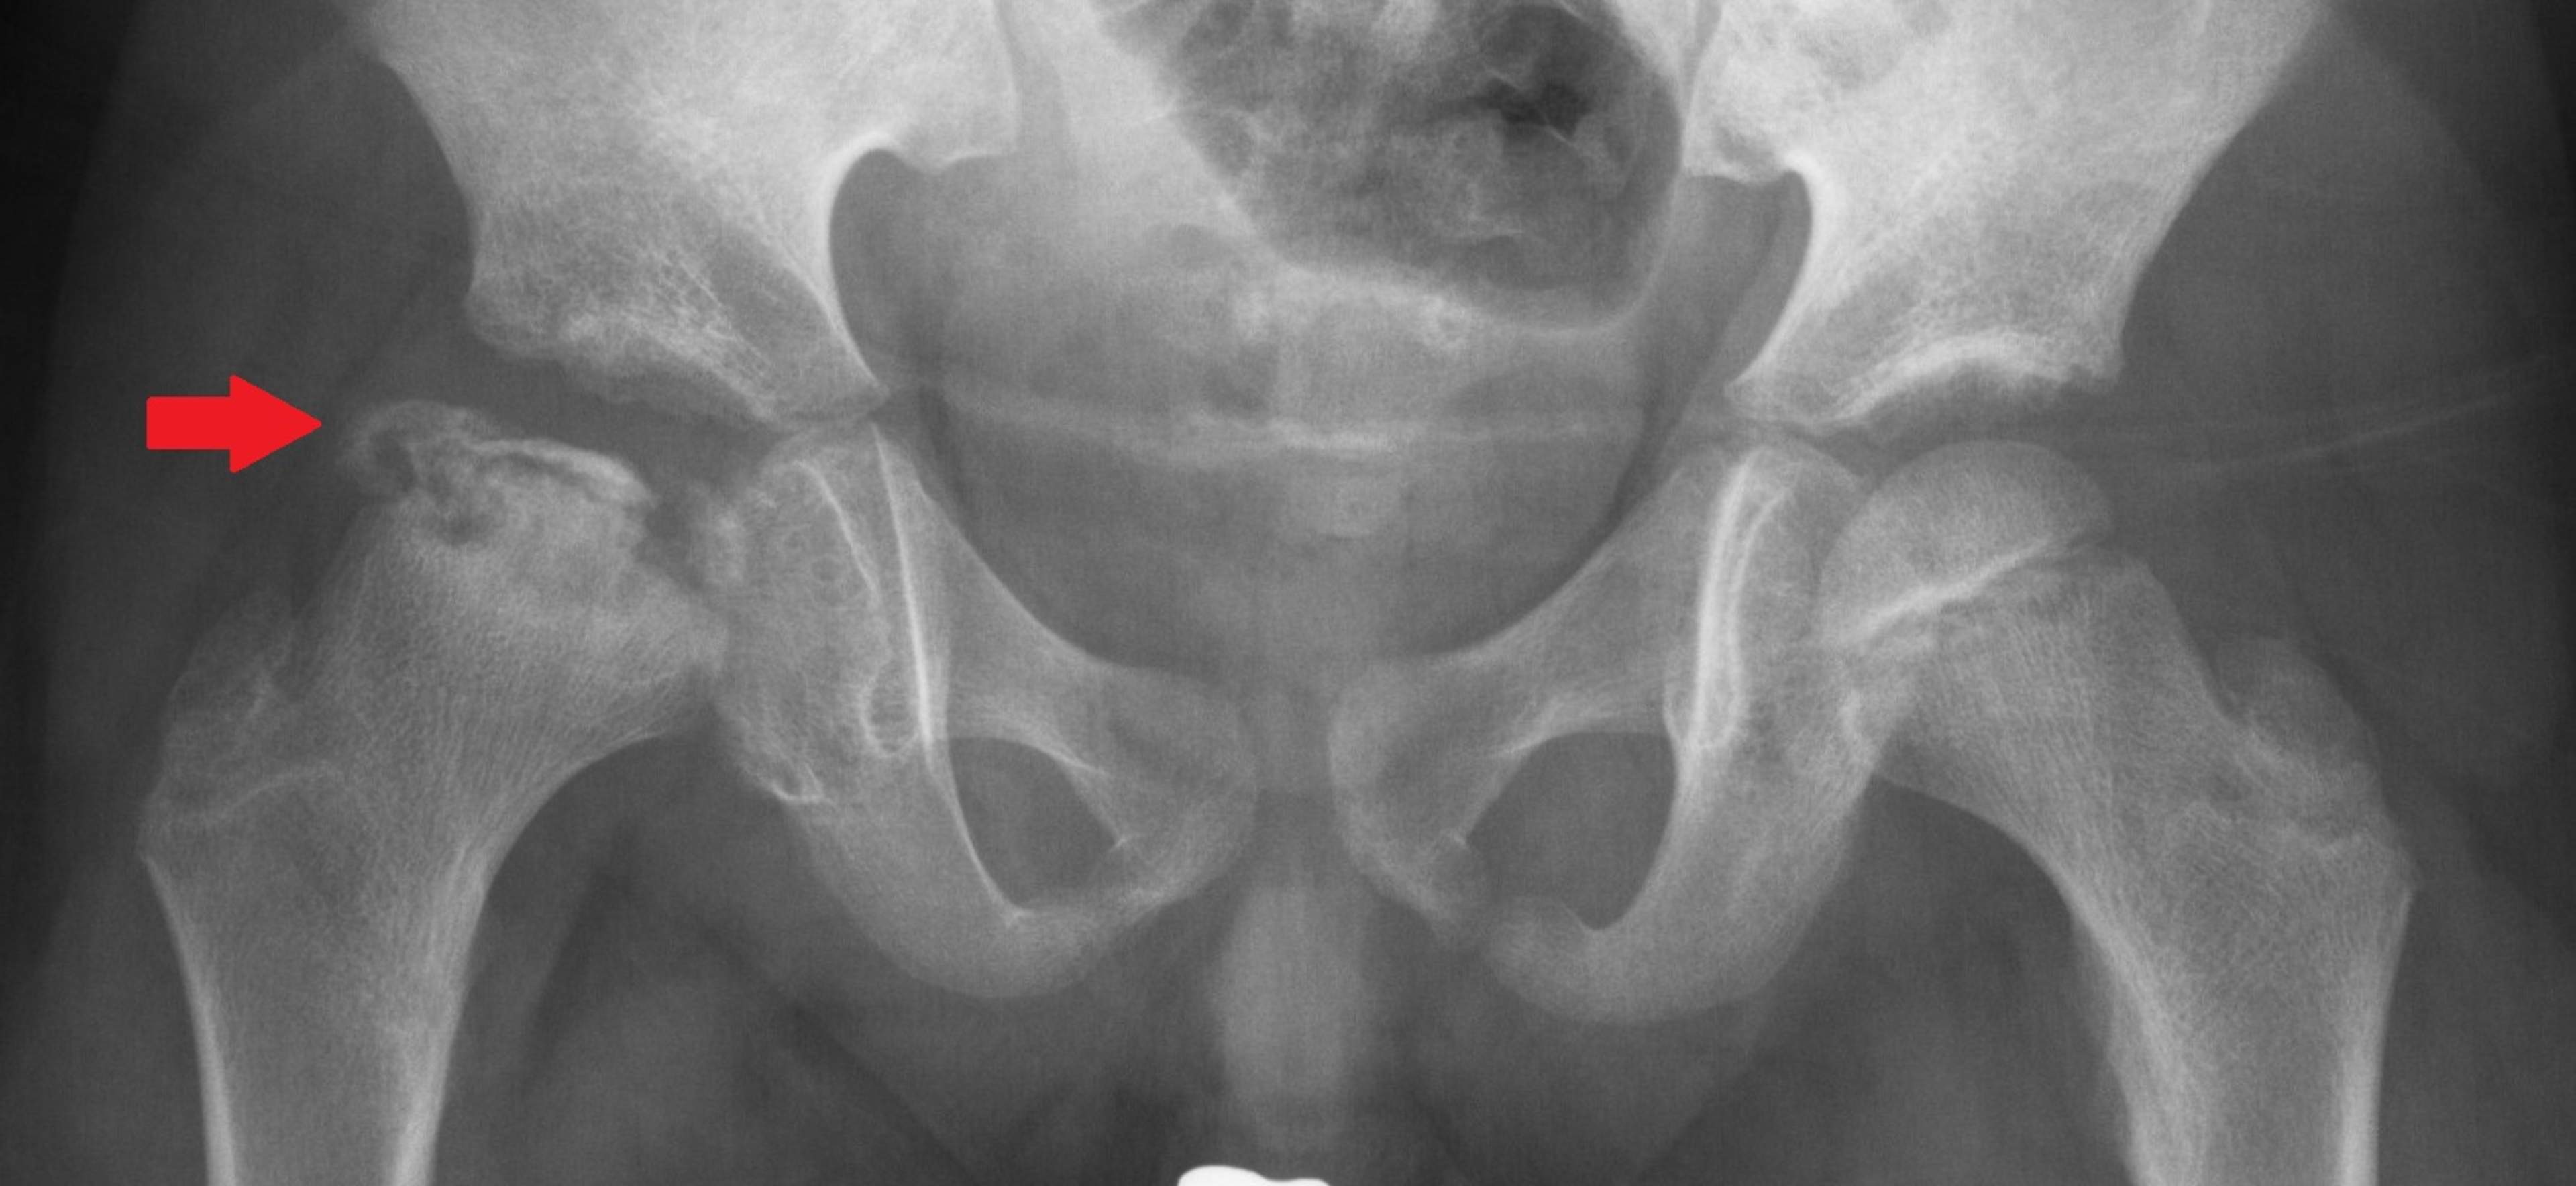

Legg-Calvé-Perthes sjukdom orsakas av en störning i blodcirkulationen i lårbenshuvudet, vars orsak är okänd. Störningen i blodcirkulationen leder till delvis nekros i lårbenshuvudets förbening, på grund av vilket lårbenshuvudets form förändras och det uppstår begränsad rörlighet och smärta i höften. Sjukdomen förekommer hos barn i lek- och skolåldern, oftare hos pojkar än hos flickor. Läkningsprocessen kan ta flera veckor. Prognosen är oftast god om sjukdomen bryter ut före förskoleåldern. I de allvarligaste fallen kan sjukdomen leda till rörelsehinder i höften, benlängdsskillnad och för tidig artros i vuxen ålder.